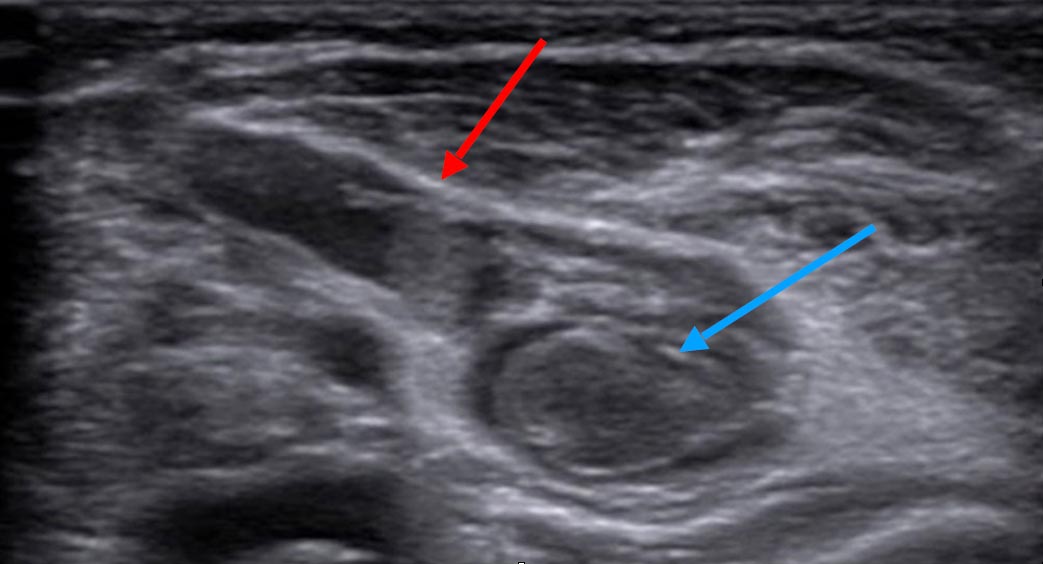

If imaging is ever necessary, sonography is the first choice. Thrombophlebitis is easily visualized within the anechoic venous malformation components as echogenic, non-compressible circumscribed foci.

On sonography, a normal vein or venous malformation is soft and readily compressible with the transducer. The non-clotted blood is virtually anechoic (black), and slow blood flow is detectable on color-coded duplex sonography.

As the blood clot matures with time, it becomes more echogenic sonographically, making it easy to distinguish from anechoic blood. Often starting at the edge, i.e., at the vessel wall, there is a slow recanalization of the involved vessel. This is visible as anechoic fluid around the echogenic thrombus.